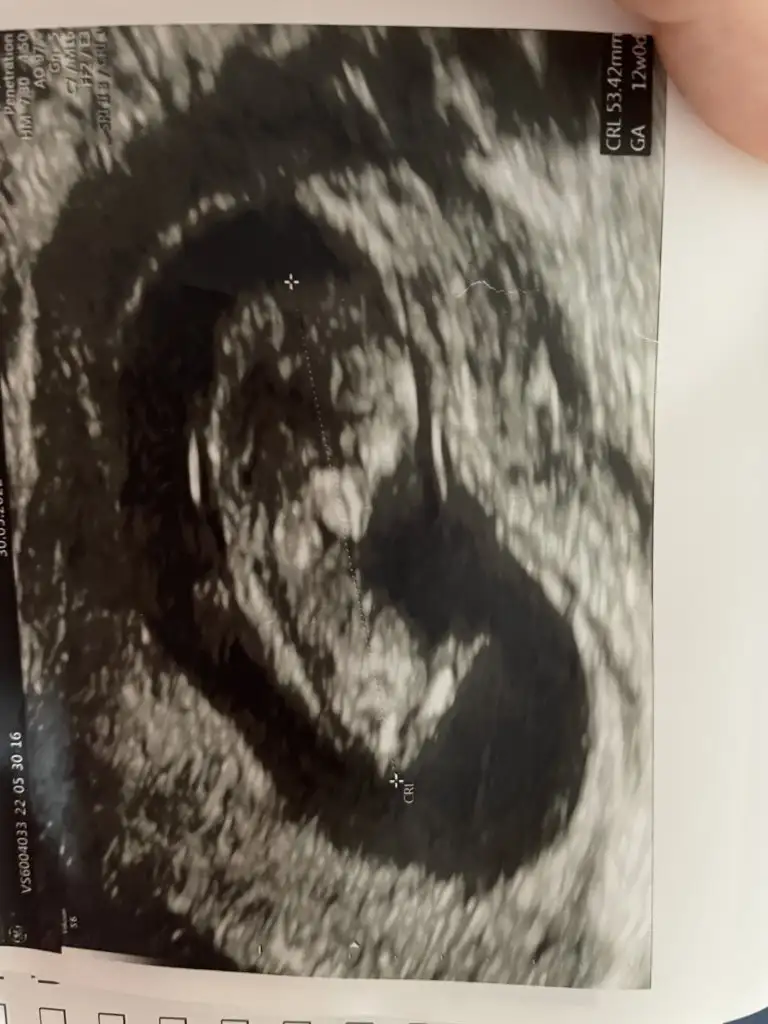

Kızlar merhaba karından ultrasonla bakıldı 10+6 cinsiyet tahmininiz nedir? 🤭 teşekkürler 🌸

• 18EE6BE5-7A40-45B3-9F6F-02162D0FD371.webp

18EE6BE5-7A40-45B3-9F6F-02162D0FD371.webp

11,7 KB · Görüntüleme: 67